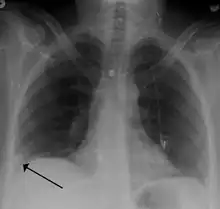

• Chest X-rays are often done on people with shortness of breath to help rule-out other causes, such as congestive heart failure and rib fracture. Chest X-rays in PE are rarely normal,[68] but usually lack signs that suggest the diagnosis of PE (for example, Westermark sign, Hampton's hump).